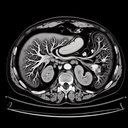

МРТ нирок

Магнітно-резонансна томографія (МРТ) нирок—це неінвазивний метод діагностики, який використовує магнітні поля та радіохвилі для отримання детальних зображень нирок та сечовивідних шляхів. МРТ допомагає виявляти: 1. Аномалії структури нирок...